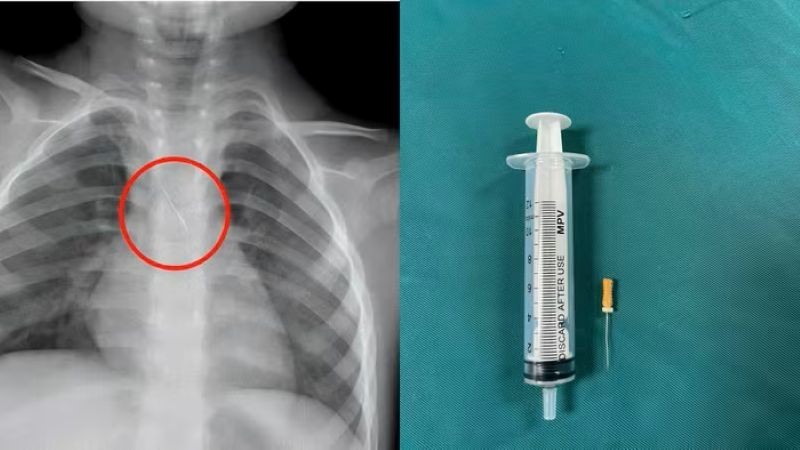

Quảng Trị: Kịp thời cứu cháu bé bị kim chọc tủy rơi vào đường thở

Sunday 2025-11-16 08:23Ngày 15/11, Bệnh viện Đa khoa tỉnh Quảng Trị cho biết vừa cấp cứu thành công một cháu bé 3 tuổi bị kim chọc tủy dài 22mm rơi vào đường thở. Dị vật trong đường thở của bệnh...